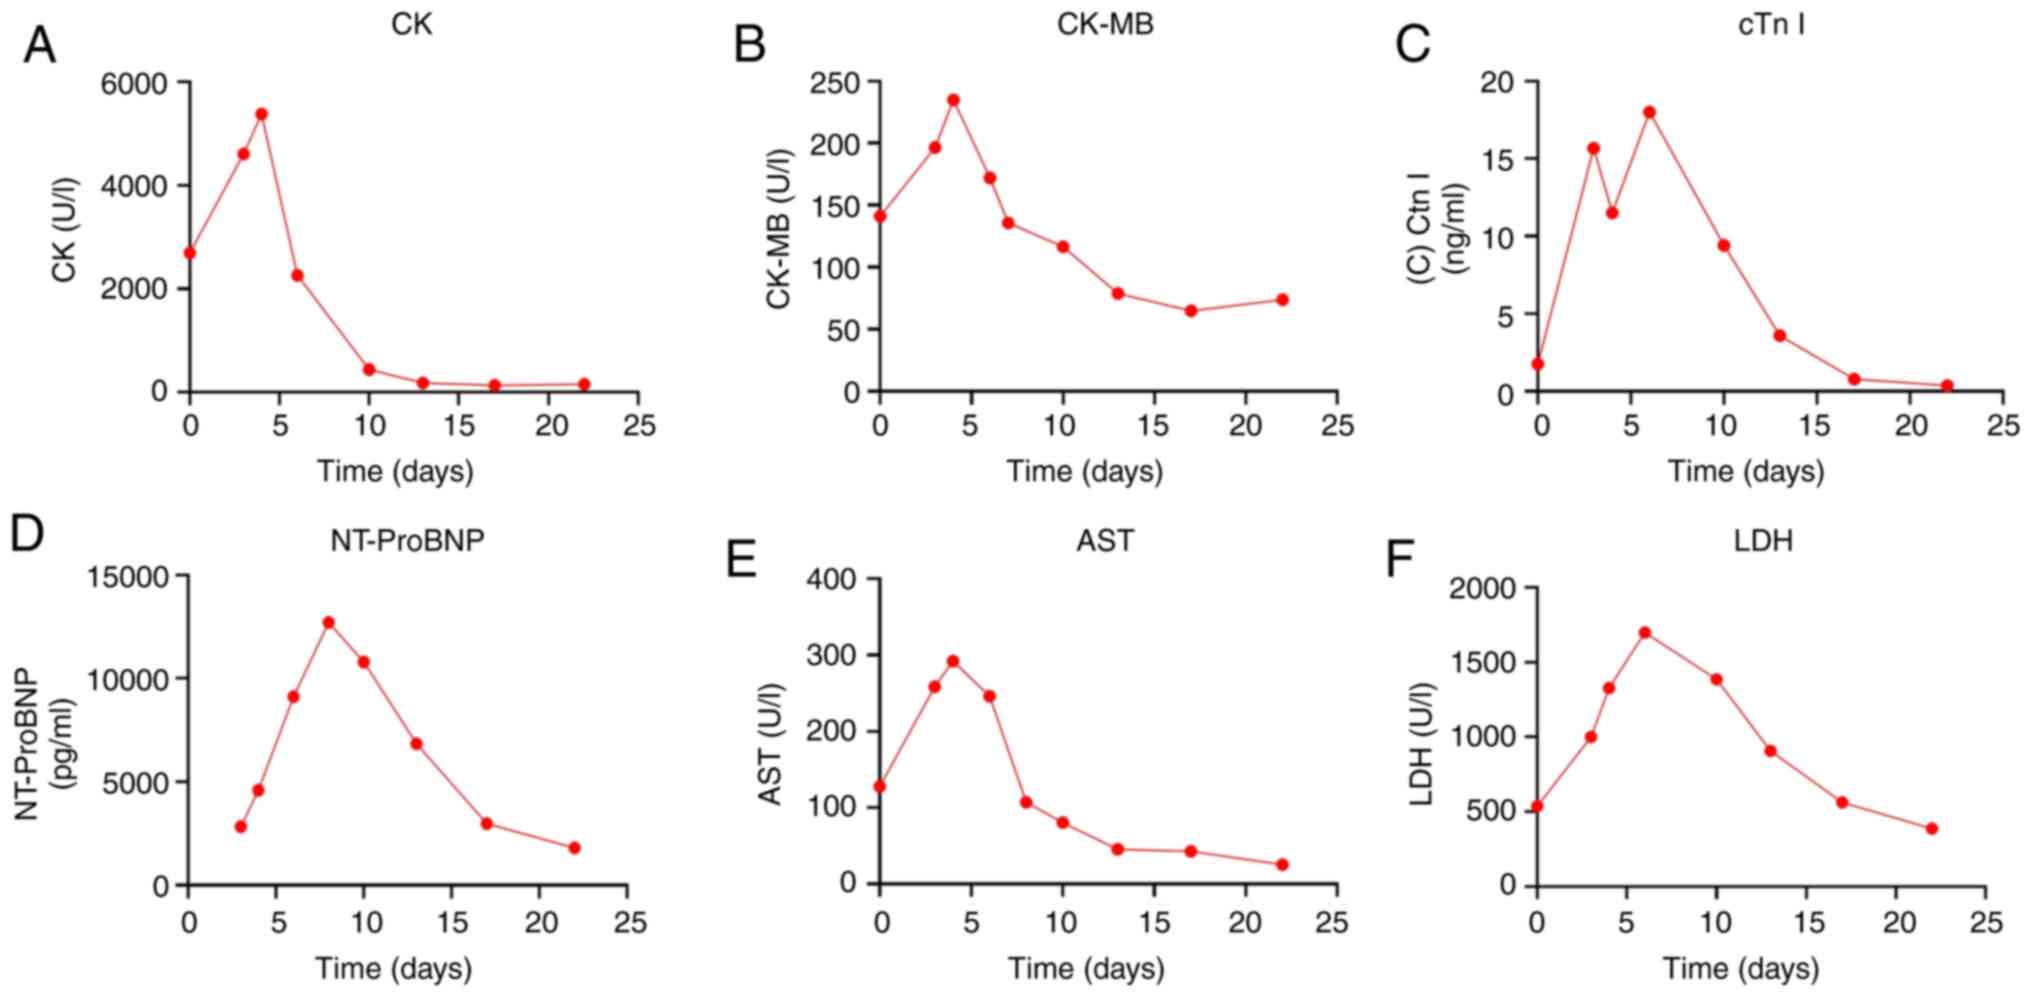

Creatine kinase (CK) was 2263.2 U/l (reference values, 40-200 U/l),

9,121 pg/ml (reference values, 0-300 pg/ml), as presented in

of the myocardial enzyme profile was performed (Fig. 5). The N-terminal brain-lysergic

enzyme spectra review on Day 10 demonstrated that the patient's

22. The cardiac enzyme markers improved significantly, indicating a

| Figure 5Changes in myocarditis-related

indicators during hospitalization. Changes in (A) CK, (B) CK-MB,

(C) cTn I, (D) NT-proBNP, (E) AST and (F) LDH. CK, creatine kinase;

CK-MB, creatine kinase isoenzymes; cTn I, cardiac troponin I;

NT-proBNP, N-terminal pro-brain natriuretic peptide; AST, aspartate

aminotransferase; LDH, lactate dehydrogenase. |

| Table IChanges in myocardial enzyme

profiles. |

Table I

Changes in myocardial enzyme

profiles.

| | Day | |

|---|

| Myocardial

enzyme | 0 | 6 | 10 | 13 | 22 | Reference

values |

|---|

| cTn I, ng/ml | 1.761 | 18.010 | 9.401 | 3.598 | 0.383 | 0.000-0.028 |

| LDH, U/l | 537.1 | 1,699.4 | 1,385.7 | 906.7 | 388.2 | 120.0-250.0 |

| CK, U/l | 2,693.2 | 2,263.2 | 443.7 | 183.5 | 158.1 | 40.0-200.0 |

| CK-MB, Ul | 141.2 | 172.0 | 116.6 | 78.9 | 73.9 | 0.0-25.0 |

| NT-proBNP,

pg/ml | 2,834 | 9,121 | 10,796 | 6,849 | 1,808 | 0-300 |